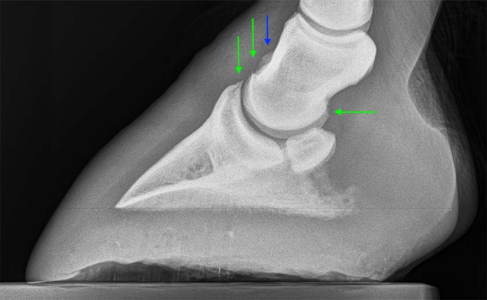

May 23 to March 25, the difference is very clear. Sorry B, even if that isn't the cause of the current lameness you've got a definite issue there. I would personally be particularly worried about how and why the joint is being pushed apart in the middle.

Considering the below image is one used as an example of a coffin joint someone has used arthramid on, I would definitely send that off for a second look by another vet, I think the remodelling of that bone is quite apparant at the top in that joint.

I would also say that comparatively, Larry's looks to have bony proliferation along the bottom of the coffin bone also.

Not from what I can see and from what I see on other x rays of good joints. The joint space shouldn't, I don't think, have got bigger in the middle like that and the culprit looks like arthritis at the front, commonly called low ringbone.